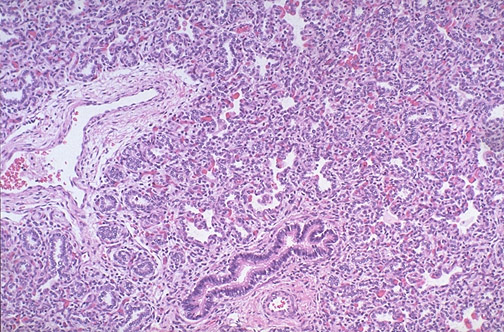

This is not my photo, see Introduction to histopathology.

LUNG TISSUE EXAMPLES